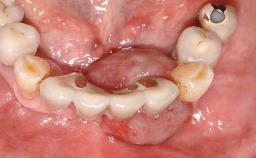

A 35-year old female patient was referred to the Department of Oral Surgery and Stomatology at the University of Bern, Switzerland, for examination of an implant site that had exhibited clinical signs of slightly delayed wound healing. In addition, the referring clinician found no evidence for a facial bone wall when she raised a flap to gain access to the implant for abutment connection. Four months earlier, she had inserted a bone-level implant in a single-tooth gap, where the lateral incisor had been extracted due to a chronic periapical lesion on the mesial aspect of the root. Implant placement was combined with simultaneous bone augmentation using deproteinized bovine bone mineral (DBBM, Bio-Oss®; Geistlich, Wolhusen, Switzerland) and a collagen membrane (Bio- Gide®; Geistlich), followed by primary wound closure. The patient also provided the postsurgical radiograph that displayed the implant with a 3.5-mm healing cap.